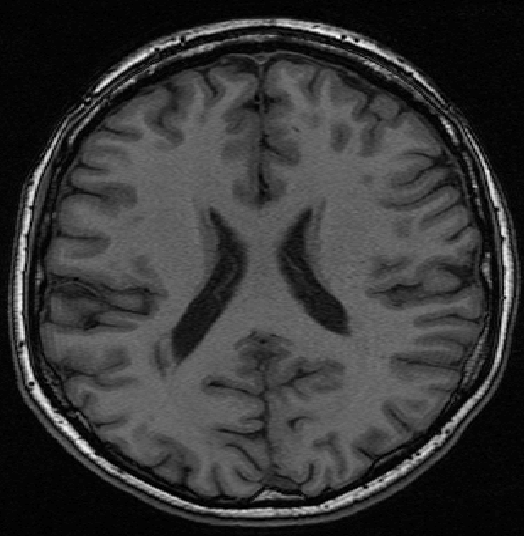

We use images from three different studies (see Fig. 1 for examples of slices):

10 MS patients from the MS Lesion Challenge [11] scanned at the Children’s Hospital of Boston (CHB), scanned with T1, T2 and FLAIR at 0.50.50.5mm resolution.

10 MS patients from the MS Lesion Challenge [11] scanned at the University of North Carolina (UNC), scanned with T1, T2 and FLAIR at 0.50.50.5mm resolution.

- 3.

Here again the differences between study populations influence the class priors. On average, the percentage of voxels that are lesions are 1.6%, 2.6% and 0.2% in CHB, RSS and UNC respectively. The differences between subjects also vary: these are relatively small for CHB and UNC, but very large for RSS. In RSS, the subject with the least lesion voxels has only 0.08%, while the patient with the most lesion voxels has 14.3%.